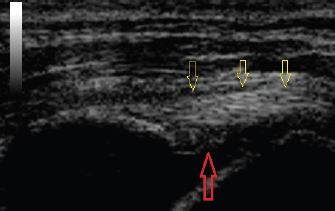

Fig. 5. Longitudinal ultrasound image of a transected biceps tendon. The intact tendon is indicated with red arrows and the point of transection with a green arrow.

Ultrasound verification of complete tendon transection was demonstrated if the tendon remained lax proximally as it spanned the glenohumeral joint, even though the limb position had not changed (Fig. 4). The tendon’s appearance, following transection, could be compared to the images taken earlier, as needed. Longitudinal and transverse imaging was also performed over the transection site to demonstrate a complete absence of tendon fibers (Fig. 5). If incomplete transection was observed, the ultrasound probe was removed and the procedure repeated until complete transection occurred. On two occasions there was discordance between the second researcher’s assessment of the complete transection based on palpation, compared to ultrasound findings. On both those occasions, it was elected to proceed with dissection rather than resume the transection.